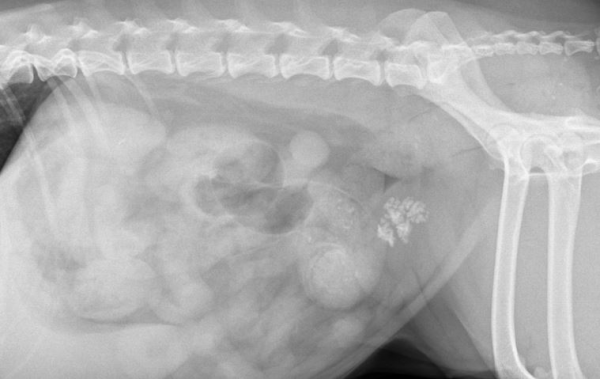

de70cef8385ff32e9ecfc65bf523daeb_1766384028_1273.png

└까미(까명) 방광결석 방사선

까미는 방광, 요도, 신장에 결석이 있는 상태로 진단되었습니다.

다행히도 요도 결석이 요도 완전폐색을 유발하지 않은 상태라

응급 수술을 요하지는 않았습니다.